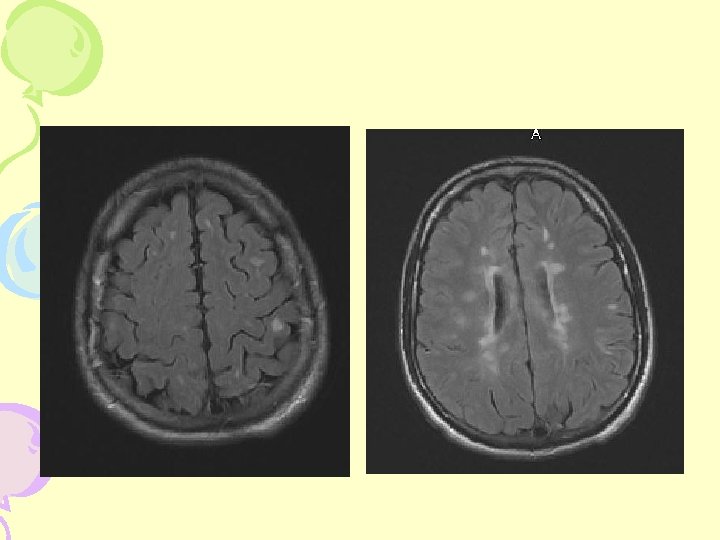

MRI- Cerebral Hemisphere

T 1 nn „black holes“